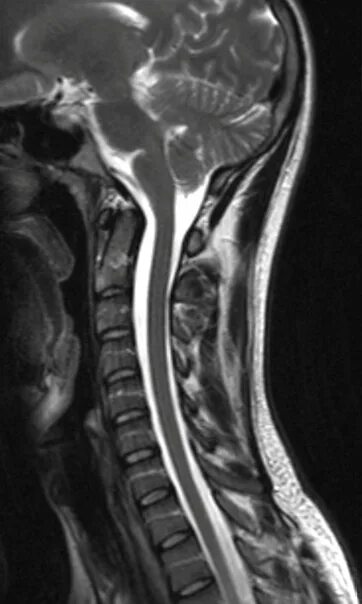

Мрт 8